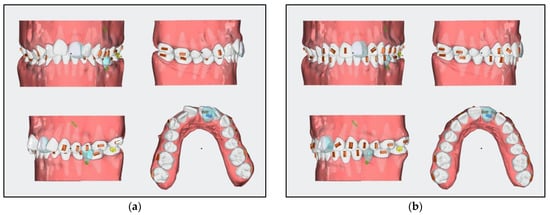

- For aligner stages 1 to 16, a mini screw in the area between teeth 34 and 36 was added for the distalization and uprighting of teeth 36 and 37.

- A segment of braces was used to distalize teeth 36 and 37, employing the mini screw as skeletal anchorage. The segment of braces consisted of two metal brackets on teeth 36 and 37, a piece of stainless steel archwire of size 16 × 22, and a heavy-force 9-mm closed-coil spring. The length of the archwire used was measured by adding 2 mm to the distance between the mini screw and tooth 37, leaving space for the teeth to slide distally.

- The distalization of teeth 16, 17, 26, and 27 was planned with aligners by adding Class II elastics of 6 Oz and a quarter of an inch.

- A horizontal attachment was added onto the temporary crown of tooth 21 for distalization using the implant as skeletal anchorage.

- After stage 16, rescanning should be carried out, and the space for the implant surgery of tooth 35 should be evaluated.